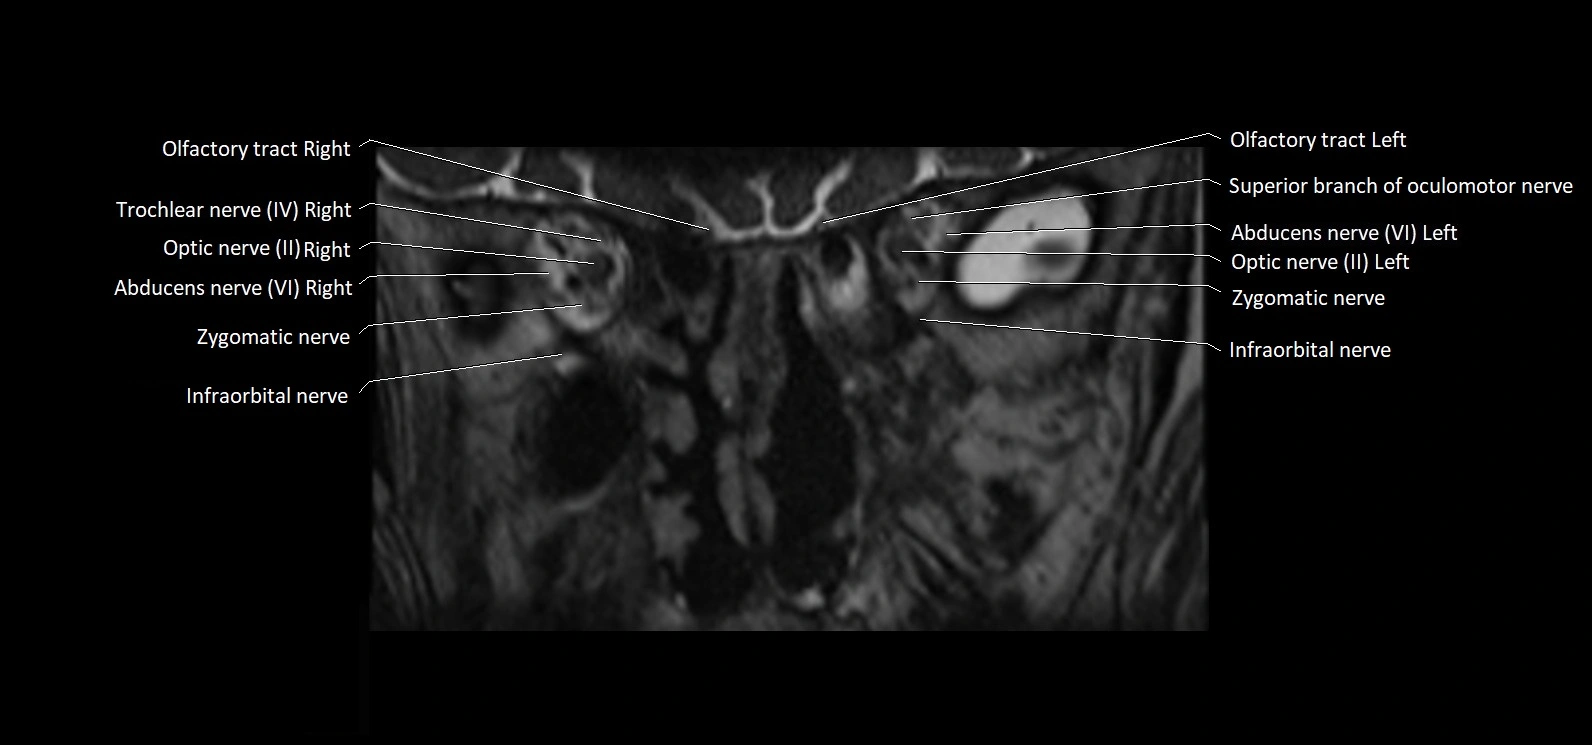

MRI Appearance

• The abducens nerve is a small, thin, linear structure

• Best visualized on high-resolution T2-weighted 3D MRI sequences (e.g., FIESTA or CISS)

• Seen as a hypointense (dark) line running from the brainstem at the pontomedullary junction, traversing the prepontine cistern, and entering Dorello’s canal under the petrosphenoidal ligament, then into the cavernous sinus, and finally the orbit

• May be challenging to visualize in standard MRI due to its small size

• Pathology may be inferred by absence, displacement, or enhancement of the nerve

MRI images

image